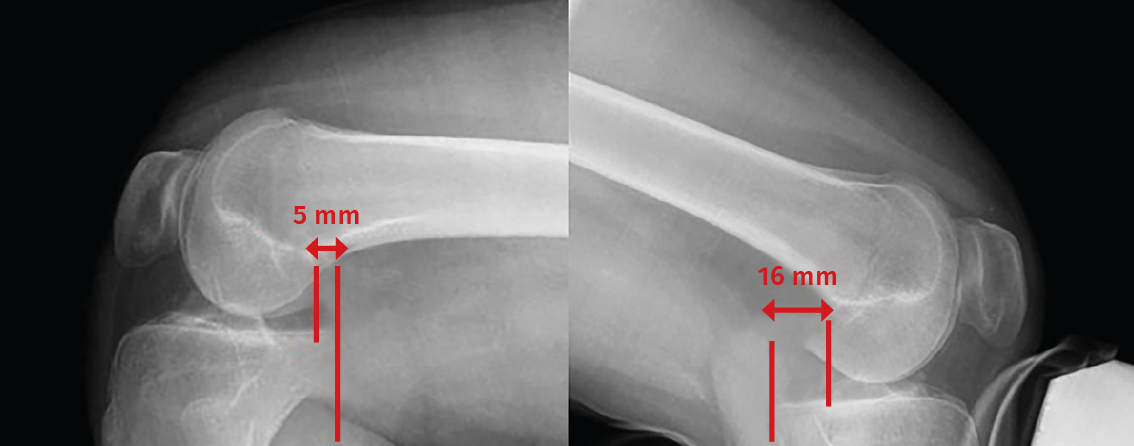

Stress radiography

Comparative stress radiographs play an important role, since they allow us to quantify and visualize posterior tibial sag in PCL injuries and assess possible associated sagittal instabilities(12,13).

• Hamstring contraction view: this is obtained with the patient seated and the knee flexed 90°. While the patient is instructed to perform maximum ischiotibial (hamstring) contraction against resistance placed at the level of the calcaneus, a strict lateral view of the knee is obtained. By comparing the profile of both knees, we can determine whether ischiotibial contraction causes posterior displacement of the tibia(12,13).

• Kneeling view: the patient kneels down on a platform reaching the anterior tibial tuberosity. The knees are to be in 90° flexion and the hips in 180°. A strict lateral view is obtained of both knees, evaluating the difference in posterior tibial translation. This view simulates quantification of the posterior drawer test, and is the easiest view to obtain and also the most widely used in clinical practice(12,13).

• Telos® system: this system allows us to apply constant and quantifiable force to the knee in different planes. If we wish to evaluate the PCL, the force is exerted on the anterior tibial tuberosity with the knee flexed 90°. A strict lateral view is obtained of both knees, evaluating the difference in posterior tibial translation(12,13).

The classification of PCL injuries according to the observed posterior translation is as follows:

– Partial injury of the PCL if there is an increase in posterior translation of <8 mm.

– Isolated complete injury if translation is between 8-12 mm.

– Injury of the PCL with other associated lesions (posterolateral or posteromedial) if there is >12 mm of posterior translation.

Posterior translation of the tibia is measured as the minimum distance between a line tangential to the posterior cortical layer of the tibia and another line tangential to the posterior margin of the femoral condyle at the most dorsal point of the Blumensaat line (Figure 5)(12,13).

Figure 5. Telos system. The red line indicates measurement of posterior translation of the tibia: the difference between the healthy right knee and the left knee is 11 mm in this case - suggestive of isolated complete posterior cruciate ligament (PCL) rupture.